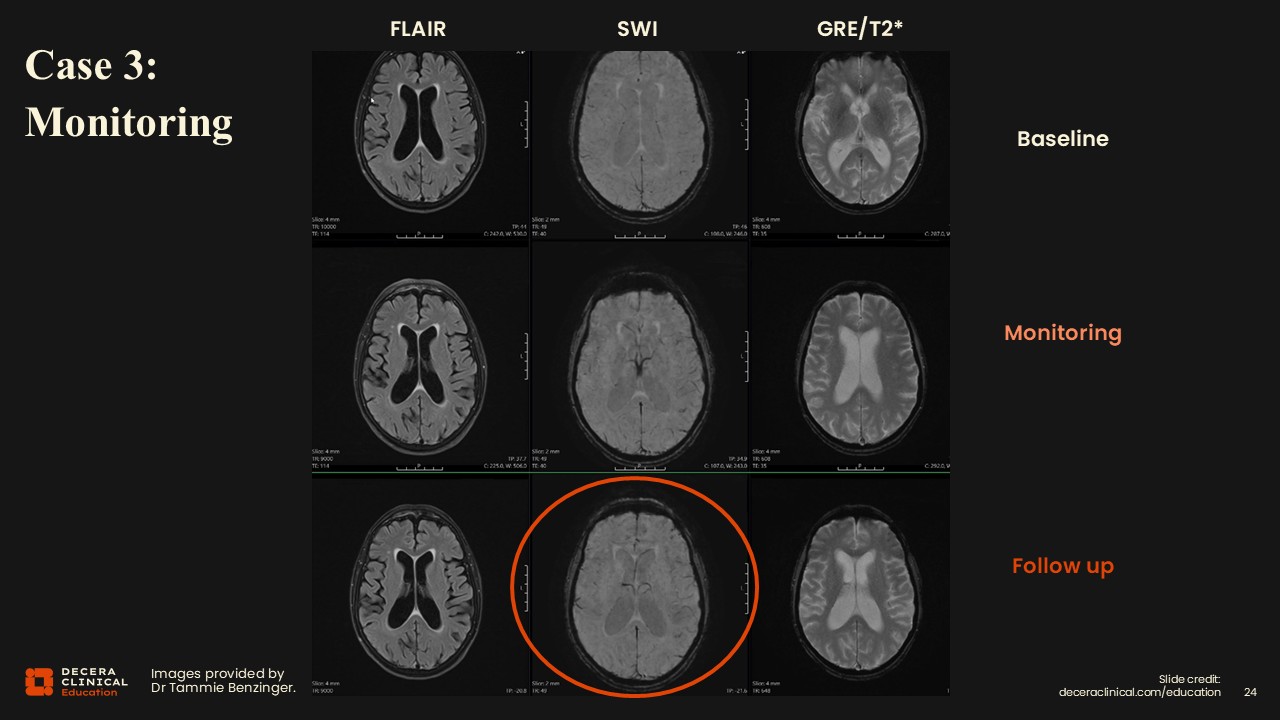

This case represents a new patient on ATT. As with the other cases, we have a FLAIR, an SWI, and a GRE/T2*.  The findings here are very subtle.

Consider the image in the middle on the bottom, circled in red. In the left frontal lobe, subtle darkness or loss of signal can be seen, which is new compared with baseline imaging. On careful review, it is associated with a very subtle effusion and edema. This ARIA-E was missed on the middle monitoring visit.